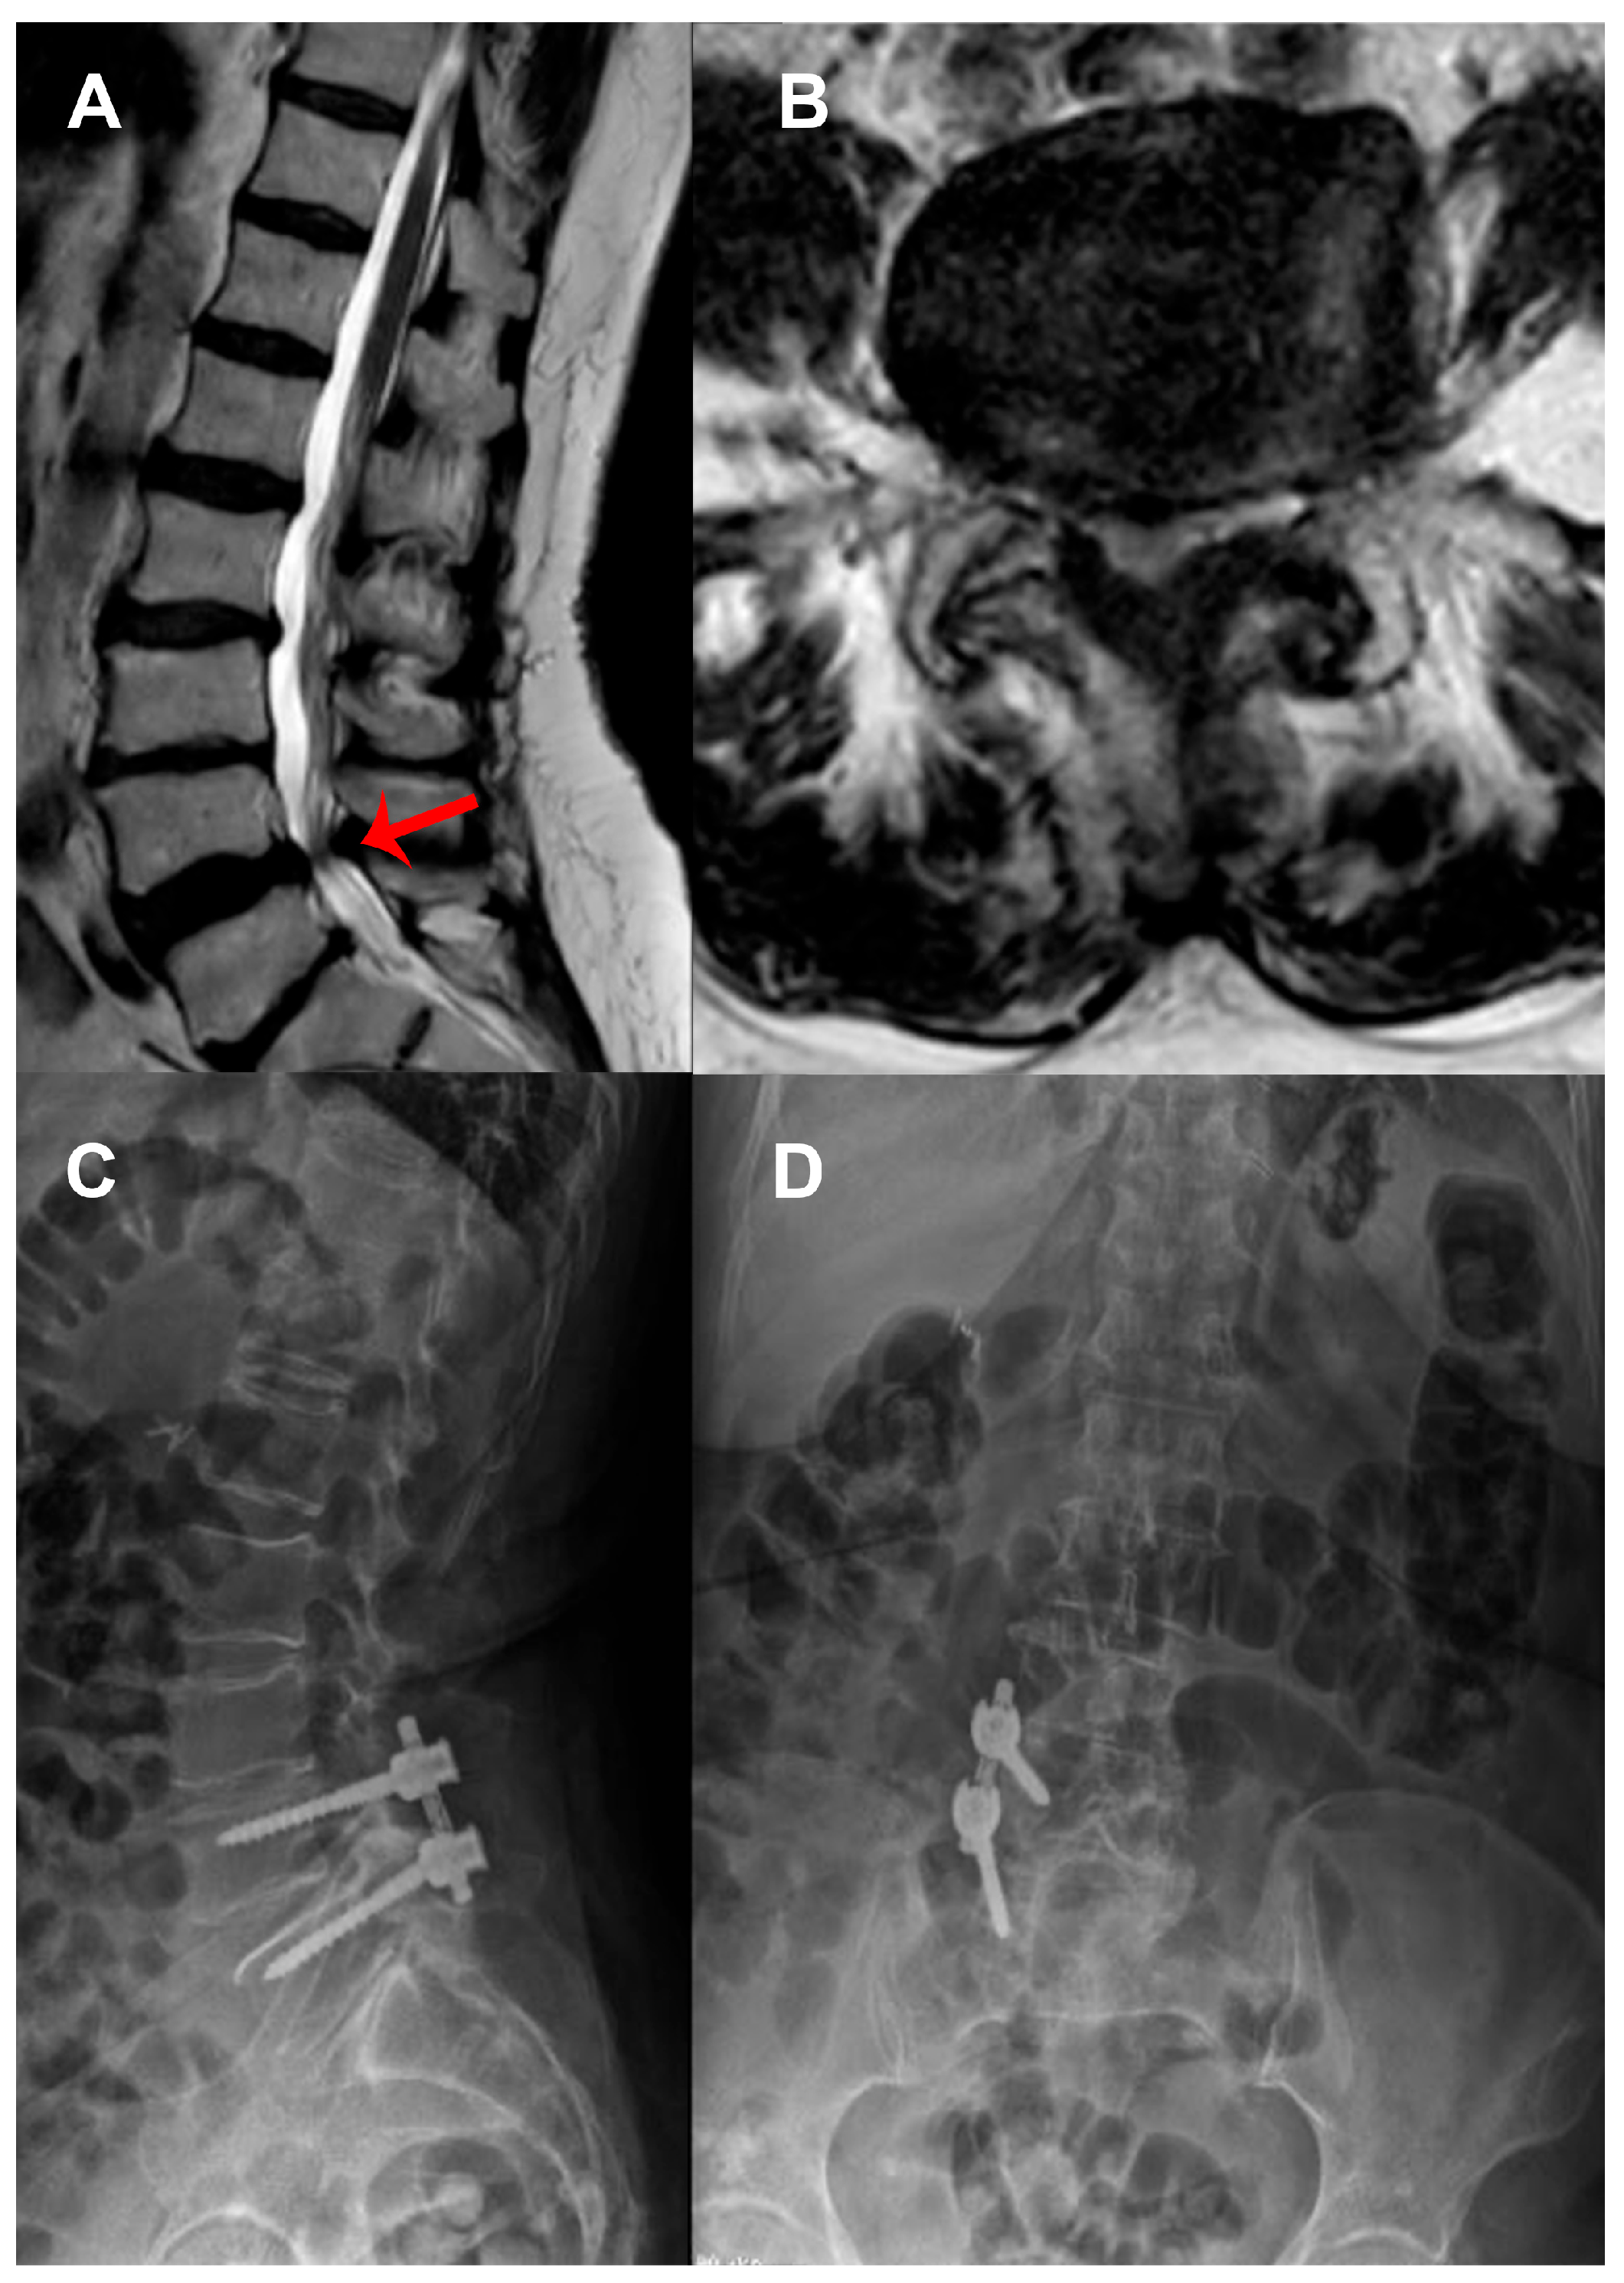

2.3. Surgical Technique